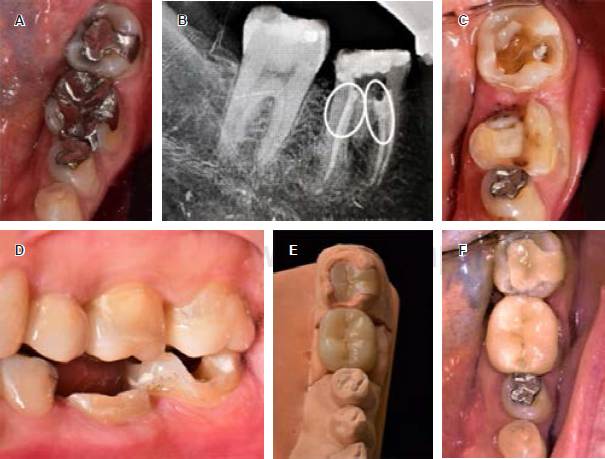

Mujer de 48 años con síndrome de Sjögren secundario acude a consulta para tratamiento integral a la misma clínica de la misma institución. Para rehabilitar los dientes 37 y 36, se eliminan las obturaciones previas y la remoción de lesiones de caries circundante y en cervical del diente 36 (Figura 2A), donde se evidencia gran pérdida de tejido tanto coronal como radicular, con el diagnóstico endodóncico de pulpitis irreversible asintomática, se procede a realizar el tratamiento de conductos, se observa una raíz cónica y una disposición de conductos en C (Figura 2B-C). Terminado el tratamiento de conductos, se determina la colocación de una endocorona ante la imposibilidad de retención de un poste intrarradicular por la disposición de los conductos y el grosor de las paredes radiculares. Se sella el tercio cervical con ionómero de vidrio fotopolimerizable VitrebondTM (3M-ESPE) (Figura 2D).

Figura 2 A) Restauración de amalgama previa en diente 36. B) Una vez retirada la obturación y remoción de caries en zona lingual comprometida. C) Radiografía final del diente después de realizar el tratamiento de conductos y restauración temporal. D) Conductos en forma en C, antes de sellar su acceso con ionómero de vidrio. E) Restauración ya cementada después de verificada la oclusión.

En la siguiente cita, se conforman las paredes intrapulpares y la zona lingual comprometida con fresa troncocónica 856 (Figura 2B), se eliminó todo tejido remanente frágil y se terminó la preparación coronal y se obtuvo la impresión con PVS Virtual® XD (Ivoclar Vivadent), determinando como material restaurativo final cerómero y se coloca obturación temporal. En la tercera cita, se procede con la prueba y consecuente cementación de la restauración de SR Nexco (Ivoclar Vivadent) con cemento RelyXTM U200 (3M-ESPE), se realizó la remoción de excedentes, el control de oclusión y pulido final (Figura 2E).

Mujer de 57 años de edad, acude también a la misma clínica a consulta para cambio por desajuste de restauraciones metálicas de amalgama e incrustación metálica en dientes 36 y 37 respectivamente (Figura 3A). Después de la remoción de las restauraciones metálicas y la limpieza de éstas se evidencia la necesidad de tratamiento de conductos en diente 36 por diagnóstico de pulpitis irreversible asintomática. Durante la permeabilización de los conductos se produjo una perforación del piso pulpar, el cual se procede a sellar con un sustituto bioactivo de dentina con base en silicato tricálcico, Biodentine™ (Septodont) y se prosiguió con el tratamiento de conductos, dejando en observación el diente por una semana (Figura 3B).

Figura 3 A) Restauraciones preexistentes de dientes 36 y 37. B) Obturación de conductos y sellado de la perforación de furca con BiodentineTM (Septodont). C) Sellado con ionómero de vidrio y preparación para la endocorona. D) Comparativa de estructura remanente entre 36 y 37. E) Endocorona y onlay de disilicato de litio en modelo. F) Restauraciones cementadas.

En la segunda cita, los signos y síntomas permitieron terminar el tratamiento de conductos y sellar la cavidad pulpar con una capa de ionómero vítreo VitrebondTM (3M-ESPE) de 2 mm de espesor, por el poco remanente dentario y la imposibilidad de colocar un endoposte por la nula existencia de paredes axiales para su retención, se decide realizar una endocorona de disilicato de litio e.max CAD (Ivoclar Vivadent AG) en el diente 36 y un onlay convencional en diente 37, se procede a tomar impresión con PVS Elite HD+ (Zhermack) y se coloca resina C&B como obturación temporal (Figura 3C-E).

En la tercera cita se eliminaron las obturaciones temporales, se prueban las restauraciones cerámicas definitivas, comprobando su adaptación, áreas de contacto del diente 36, contactos interoclusales en posición céntrica, excursiones laterales y protusiva para después proceder a la desinfección del tejido remanente con pasta de clorhexidina al 2% ConsepsisTM Scrub (Ultradent), se procede al grabado de las restauraciones con ácido fluorhídrico al 9% Porcelain Etch (Ultradent) durante 20 segundos,10,11 neutralización con ácido ortofosfórico al 35% (3M), y colocación de silano por 1 minuto; la cementación fue igualmente con cemento polimérico dual RelyXTM U200 (3M-ESPE), se removieron excedentes y se realizaron los ajustes necesarios de oclusión (Figura 3F).